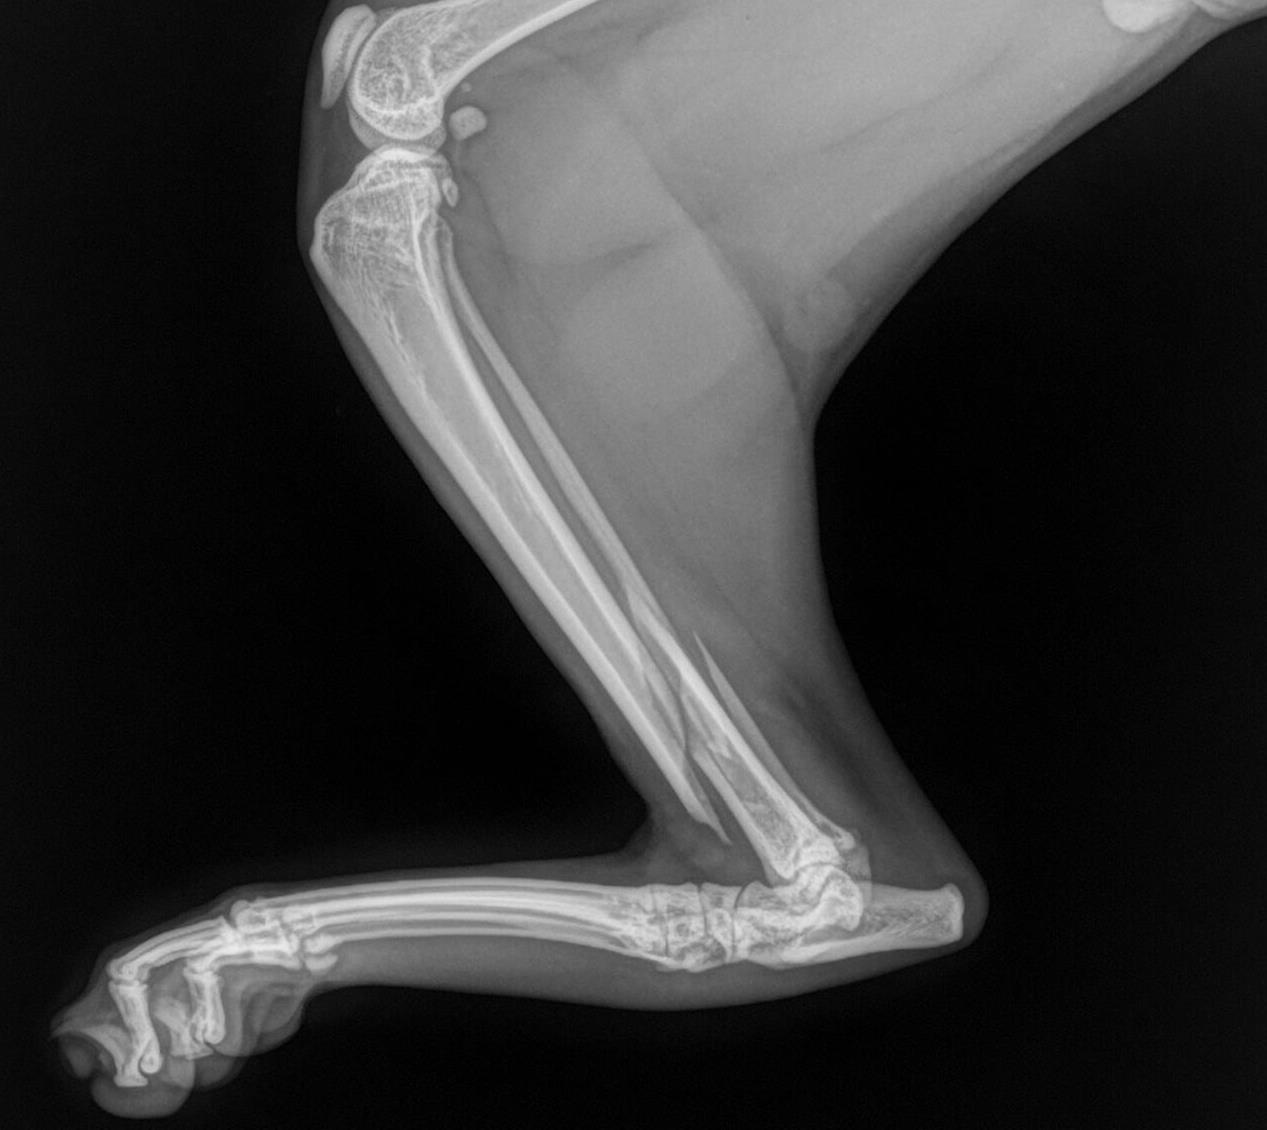

injury I think my cat broke it's leg Pets Stack Exchange How Much Does It Cost To Fix My Cats Broken Leg Some cat owners may worry about the cost of treating a broken leg in their furry friend. If you think your cat might have a broken leg, you probably need immediate answers on cost. The cost of treating a broken leg in a cat can vary widely depending on several factors, including the severity of the injury, the type of. How Much Does It Cost To Fix My Cats Broken Leg.